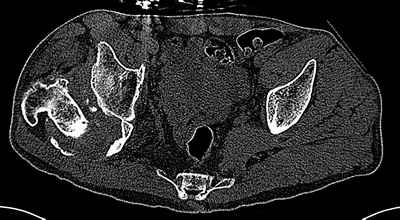

Уважаемые коллеги. Пациент 30 лет 3 года назад в результате травмы получил травматический дефект нижних конечностей до в/3 голеней, был пропущен вывих бедра.

В настоящее время очень неплохо ходит на протезах, движения в неоартрозе близки по объему к здоровой стороне. Основная жалоба - выраженная боль при ходьбе. планируем двухэтапное эндопротезирование - задним доступом мобилизовать проксимальный отдел бедра, резецировать шейку, аппаратом низвести бедро(головку оставить там где она есть, так как больших дефектов не видно(может пригодится в последующем?)). Вторым этапом бесцементное эндопротезирование. Насколько такой вариант реалистичен? Доступ для второго этапа? Может быть другие варианты? С уважением, Максим